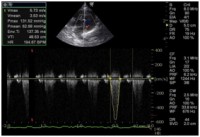

身体検査、レントゲン検査、心電図検査、超音波検査で診断します。

超音波検査では肥大した心筋を確認します。

写真は肥大型心筋症の患者さんの超音波画像です。

心筋が肥大しているために、左心室から全身へ血液が向かう部分で閉塞が起きています。